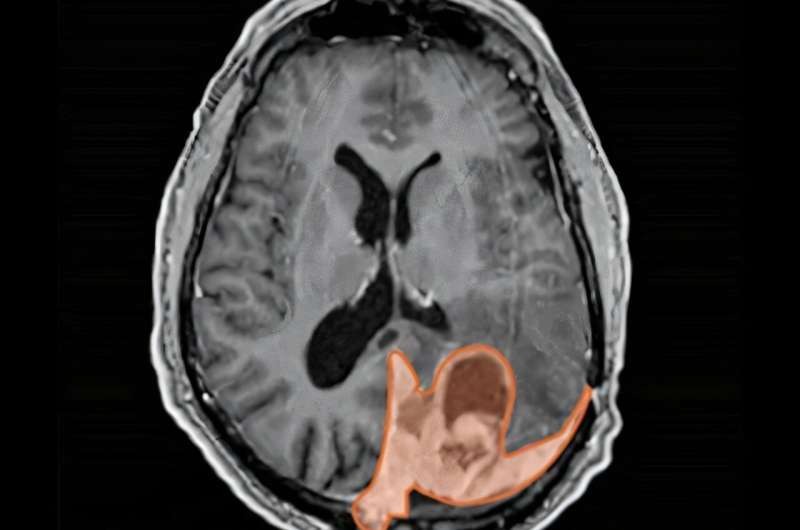

أورام المخ

تستخدم نساء كثيرات وسائل منع الحمل عن طريق الحقن العضلي، ولكن قد لا يدرك بعضهن ارتباط هذه الحقن بأورام المخ مثل الورم السحائي، وهو ما تشير إليه أبحاث علمية حديثة.

وبحث الطبيب ديفيد رالي الحاصل على درجة الدكتوراه، أخصائي الأورام الإشعاعية، حول الآليات البيولوجية التي تُغذي نمو السرطان السحائي بالمخ، واهتمت أبحاثه بفهم العلاقة بين الورم السحائي والبروجيستيرون الاصطناعي "MPA" المُستخدم في وسائل منع الحمل عن طريق الحقن، بحسب موقع "مديكال إكسبريس".

ووجد الباحثون في دراسة فرنسية أجريت عام 2024، أن النساء اللاتي استخدمن وسائل منع الحمل عن طريق الحقن العضلي لمدة عام واحد على الأقل كان لديهن خطر متزايد بنسبة خمسة أضعاف للإصابة بالورم السحائي مقارنة بمن لم يستخدمن هذه الوسائل.

يُعد الورم السحائي أحد أنواع أورام الدماغ القليلة الأكثر شيوعًا لدى النساء عن الرجال، أي أكثر شيوعًا بحوالي مرتين إلى أربع مرات.

ووفقًا للأبحاث، فإن الحمل قد يُسرع نمو الورم السحائي، وهذا النمط نفسه يُلاحظ لدى النساء اللواتي استخدمن العلاج الهرموني بعد انقطاع الطمث، وأيضًا لدى النساء اللواتي استخدمن وسائل منع الحمل عن طريق الحقن العضلي، يمكن أن يتراجع الورم السحائي بعد الولادة وبعد التوقف عن العلاج الهرموني، وتشير البيانات السريرية والوبائية بالتأكيد إلى وجود ارتباط ميكانيكي بين هذه النتائج.

ما مدى خطورة الورم السحائي؟

عادةً ما يكون ورم الدماغ خطيرًا، لكن هناك درجات مختلفة منه، تعد حوالي 65% إلى 70% من الأورام السحائية هي أورام من الدرجة الأولى ذات الخطورة العالية، وتُعتبر هذه الأورام غير خبيثة، وعادةً ما تُزال جراحيًا أو تُعالج بالعلاج الإشعاعي، وإذا بقي ورم، يُمكن علاجه أيضًا بالعلاج الإشعاعي. يبقى ما يصل إلى 95% من مرضى الدرجة الأولى على قيد الحياة بعد خمس سنوات، حسب العمر وحجم الورم المُزال.